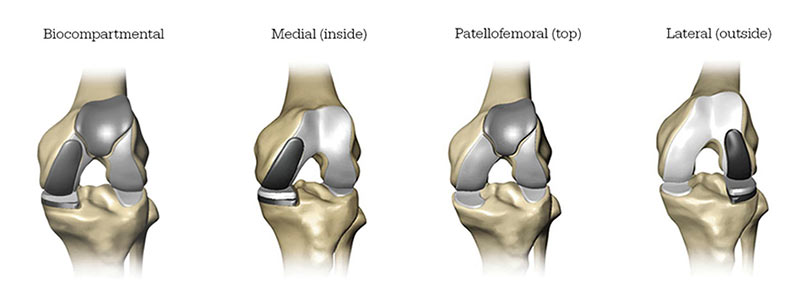

Partial Knee Replacement

A treatment option for adults living with early to mid-stage osteoarthritis (OA) that has not yet progressed to all three compartments of the knee. Depending on where the arthritis affects the knee, patients may have an implant inserted in any of the following areas:

Total Knee Replacement

A treatment option for adults living with mid to late-stage osteoarthritis of the knee. With Total Knee replacement, the entire knee joint is replaced and the surgeon inserts a Triathlon Total Knee implant. With over a decade of clinical history, Triathlon knee replacements are different than traditional knee replacements because they are designed to work with the body to promote natural-like circular motion.5-8